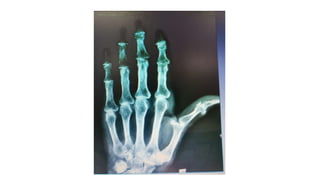

Caso clínico 3 •M.S.O.S. 66ª, Dor nas mãos há 1 ano e meio, que no início da doença era mais intensa ao acordar e diminuía ao longo do dia, porém com a progressão da doença a dor tem ocorrido o dia todo; • Rigidez nas articulações das mãos de menos de 1 hora • Inchaço nos dedos; • Dificuldade para realizar movimentos simples, como pegar um objeto ou escrever, por exemplo; • Formigamento das mãos, mesmo em repouso.

Caso Clínico 3 •Verificada a formação de nódulos nas articulações, como o nódulo de Heberden, que é formado na articulação Interfalangeana distal, e o nódulo de Bouchard, que é formado na articulação interfalangeana proximal. • Dor a palpação das Interfalangeanas distais e Interfalangeanas proximais.